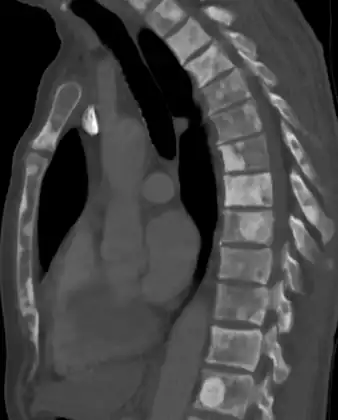

-

Sclerosis of the bones of the thoracic spine due to prostate cancer metastases (CT image) -